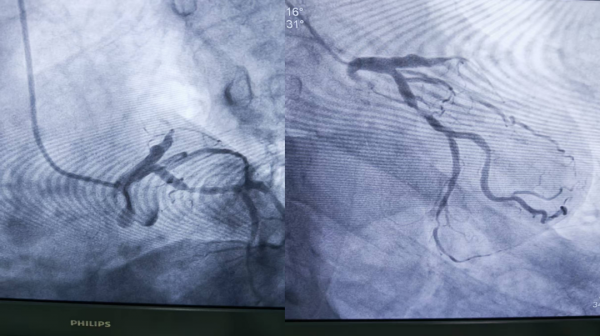

1、39岁男性,前降支闭塞,行血栓抽吸+冠脉内溶栓。

2、71岁男性,右冠闭塞,行药物球囊扩张成形术。

3、69岁男性,双支病变,行介入治疗。